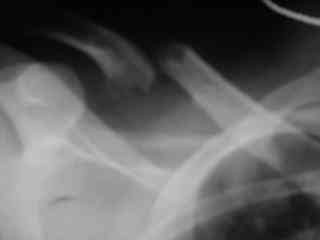

Справа перелом практически поперечный, можно попробовать интрамедуллярно стержнем. Личного опыта правда не имею, у нас стандартом при оперативном лечении переломов ключицы является тот же остеосинтез пластиной. Но в литературе описана методика даже закрытого остеосинтеза - так, в порядке обсуждения.

Bolnogo operirovali plastinami, snimky zdes'.

CIMG1145.JPG

Похоже, все прошло по плану. Поздравляю с успешной операцией!